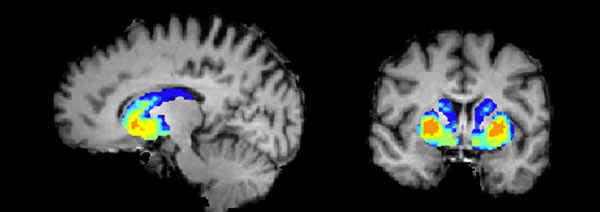

কী ভাবে কাজ হয় অ্যামিগডালায়

মস্তিষ্কের বিভিন্ন অংশ

মস্তিষ্কের যেখানে থাকে অ্যামিগডালা (লাল বৃত্ত)

মস্তিষ্কের হিপোক্যাম্পাস ও অ্যামিগডালা

বেঙ্গালুরু থেকে সুমন্ত্র বললেন, ‘‘আমাদের মস্তিষ্কে পাশপাশি দু’টি এলাকা রয়েছে। একটি- ‘হিপোক্যাম্পাস’। অন্যটি- ‘অ্যামিগডালা’। ভয়, আতঙ্ক, আনন্দ, দুঃখ, হতাশা- এমন নানা অনুভূতির জন্ম হয় ওই অ্যামিগডালায়। আর সেই সব কিছুর স্মৃতিকে আজীবন আগলে বাঁচিয়ে রাখে ওই অ্যামিগডালাই। কোনও স্মৃতিকেই সে চট করে মুছে ফেলতে চায় না। মুছে ফেলে না। আবার স্মৃতিতের ভারে খুব বেশি ‘ভারী’ হয়ে গেলে ওই অ্যামিগডালা নিজেই বেছে নেয়, কোন স্মৃতিকে সে বাঁচিয়ে রাখবে। আর কোন স্মৃতিটুকু সে মুছে ফেলবে। অনেকটা স্পুল সিস্টেমের টেপ রেকর্ডারের মতো। বাছাইটা সে নিজেই করে। প্রয়োজনে নিজেই মুছে ফেলে কিছু কিছু স্মৃতি, ‘ভারী’ হয়ে উঠতে হবে না বলে। আমরা পড়া মুখস্থ করি, এর-ওর নামধাম, টেলিফোন নাম্বার, ই-মেল অ্যাড্রেস যে মনে রাখতে পারি বহু দিন, তার জন্য কৃতিত্বটা দাবি করতে পারে ওই অ্যামিগডালাই। মস্তিষ্কের টেমপোরাল লোবের অত্যন্ত গভীরে থাকা ওই অ্যামিগডালাই আমাদের মস্তিষ্কের ‘ইমোশনাল হাব’।

মস্তিষ্কের হিপোক্যাম্পাস এলাকা

যা দেখতে খুব ছোট্ট স্নায়ুকোষ। কাঠবাদামের মতো। যত রকমের অনুভূতি রয়েছে আমাদের, তার সব কিছুরই ‘স্টোরেজ’ (জমা থাকে) হয় অ্যামিগডালায়। আমরা দেখেছি, কোনও ভয়ঙ্কর ঘটনার পর আমাদের আতঙ্কের স্মৃতির ছিটেফোঁটাও থাকে না অ্যামিগডালায়। অমন আতঙ্কের ঘটনা যে ঘটেছে, তা ওই সময় যেন মনেই করতে পারে না আমাদের মস্তিষ্ক। কারণ, সেই ঘটনার ‘ফুটেজ’ অ্যামিগডালায় তখনও নেই। এই অবস্থাটা চলে ওই ভয়ঙ্কর আতঙ্কের ঘটনার ১০ থেকে ২১ দিন পর্যন্ত। তার পরেই হঠাৎ করেই ‘বিগড়ে যেতে’ শুরু করে অ্যামিগডালা। তার মধ্যে নানা রকমের পরিবর্তন হতে শুরু করে, ধীরে ধীরে। আতঙ্কের স্মৃতিতে একটু একটু করে ভারাক্রান্ত হয়ে উঠতে শুরু করে অ্যামিগডালা। আর আমরা ‘আক্রান্ত’ হতে শুরু করি অতীতের ওই ভয়ঙ্কর আতঙ্কের স্মৃতির হানাদারিতে! আমাদের মনে তখন প্রায় সব সময়ই হামলা চালাতে শুরু করে সেই আতঙ্কের স্মৃতি। ঘরে, বাইরে সর্বত্র। আচমকা। হঠাৎ হঠাৎ। সেই জন্যই ওই মহিলার গলার হার ছিনতাইয়ের ভয়ের স্মৃতি ফিরে আসে বেশ কিছু দিন পর, যখন আসলে তিনি গোটা ঘটনাটাই প্রায় ভুলে যেতে বসেছিলেন।’’